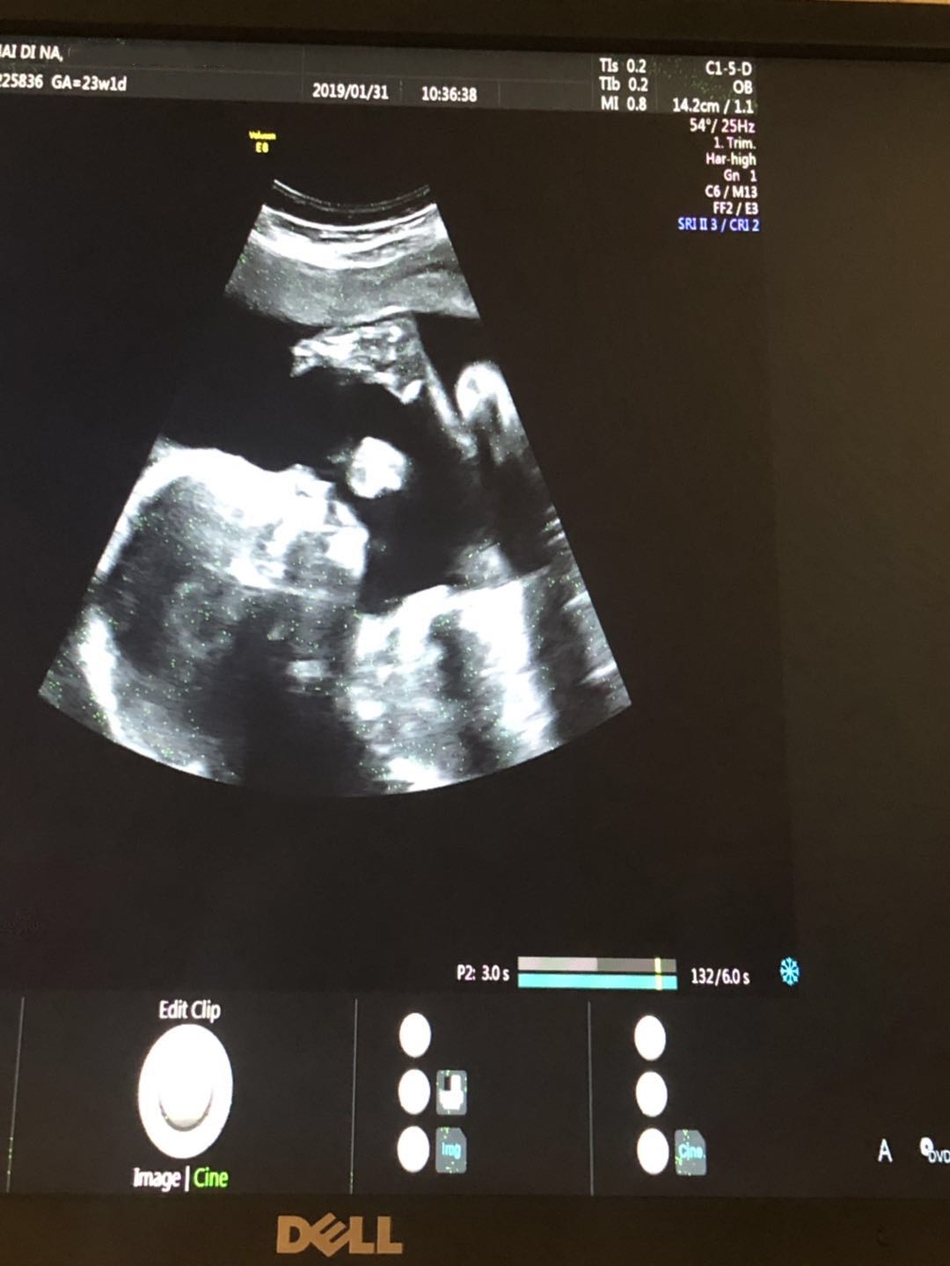

姜潮麦迪娜宝宝B超照首曝光 在妈妈肚子里吃手手超可爱

姜潮麦迪娜宝宝B超照

《新生日记》最新一期中,麦迪娜首曝宝宝的B超照,画面温馨有爱。做产检时看到宝宝的头、嘴巴、小腿时,麦迪娜、姜潮和妈妈都流露出惊喜且好奇的神情。三人的头跟着画面移动,难掩激动喜悦之情。